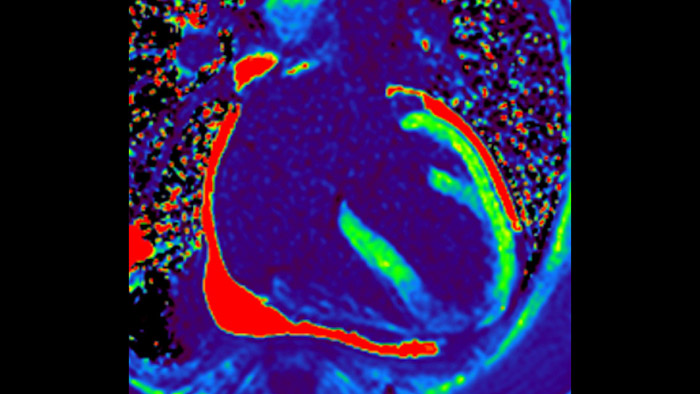

O IntelliSpace Portal MR Caas7,8 Strain9 ajuda no diagnóstico e monitorização do paciente ao proporcionar parâmetros globais de deformação, tais como deformação longitudinal global (GLS), deformação circunferencial global (GCS) e deformação radial global (GRS), utilizando imagens de RM de eixo curto e longo, bem como descrevendo a deformação do miocárdio, como encurtamento, espessamento e alongamento durante o ciclo cardíaco.